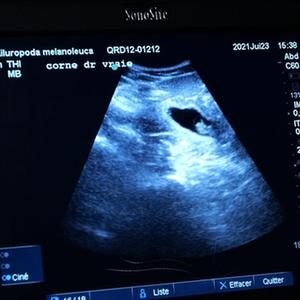

7月23日,在法国中部的圣艾尼昂市博瓦勒野生动物园,工作人员为大熊猫“欢欢”做超声波检查。

博瓦勒野生动物园当日宣布,中国旅法大熊猫“欢欢”将诞下双胞胎。

新华社发(博瓦勒野生动物园供图)